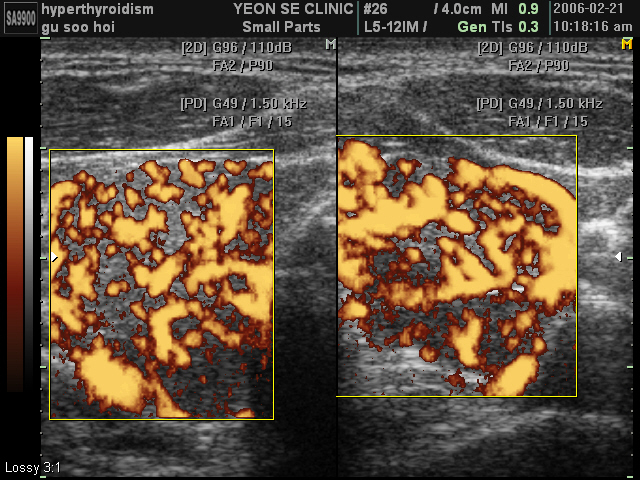

Ultrasonographic data of our patients

Graves' di...